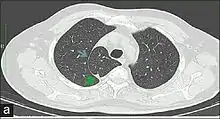

Azygos lobe

In human anatomy, an azygos lobe is a normal anatomical variation of the upper lobe of the right lung.[1] It is seen in 0.3% of the population.[2] Embryologically, it arises from an anomalous lateral course of the azygos vein,[3] in a pleural septum within the apical segment of the right upper lobe or in other words an azygos lobe is formed when the right posterior cardinal vein, one of the precursors of the azygos vein, fails to migrate over the apex of the lung and penetrates it instead, carrying along two pleural layers as the azygous fissure, that invaginates into the upper portion of the right upper lobe.[1]

An azygos lobe is usually an incidental finding on chest x-ray or CT scan, and is not associated with any morbidity.[4][5] However, it can cause technical problems in thoracoscopic procedures.[6]